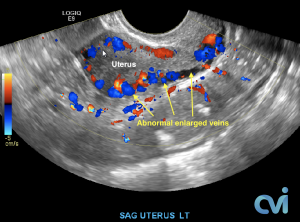

The abnormal veins dilate and cause varicose veins around the ovary and uterus because the valves don’t work properly. Blood flow is in the wrong direction, pooling in the veins and causing them to enlarge.

PCS can be diagnosed by Ultrasound or CT of the Abdomen and Pelvis.

Ultrasound examination is the least invasive study and can identify enlarged veins around the uterus and pelvis. However, sometimes the veins in the pelvis are difficult to see or can be missed if the technician is not specifically looking in the right area.